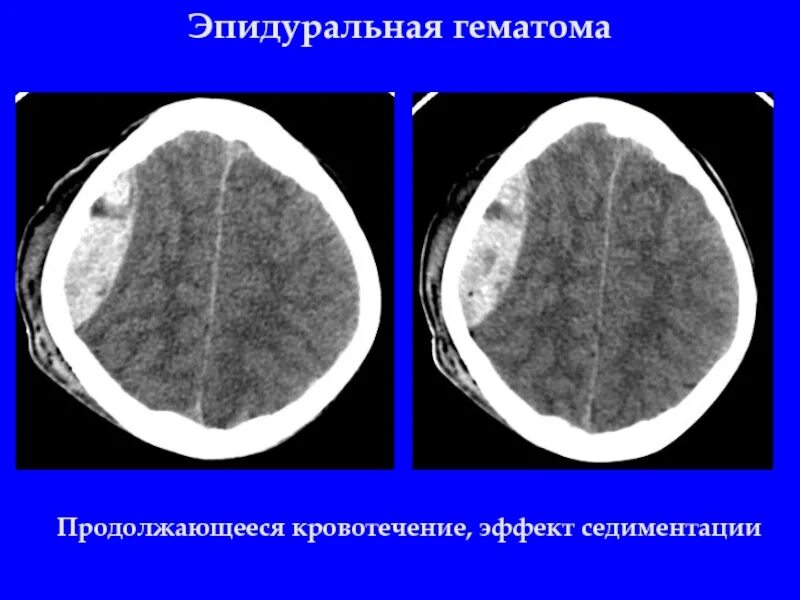

Объем гематомы на кт